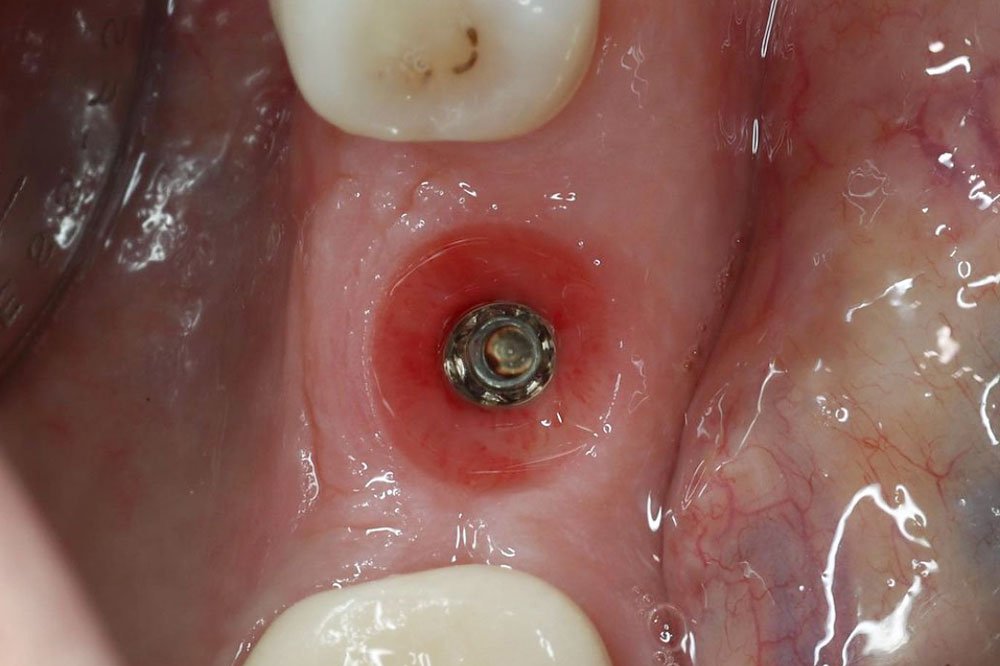

- Surgical and Prosthetic implantology

- Master Implant Surgery Protocols:Learn the step-by-step procedures for proper drilling protocols and implant placement, emphasizing the importance of precision and technique in achieving optimal results.

- Develop Competence in Complication Management:Explore common complications associated with implant surgery and learn evidence-based strategies for prevention, identification, and management of these complications.

- Acquire Hands-On Implant Surgery Experience:Perform implant surgery on a pre-selected case under the direct supervision of Dr. Dagher, applying learned techniques to real-life scenarios and receiving personalized feedback for skill development.